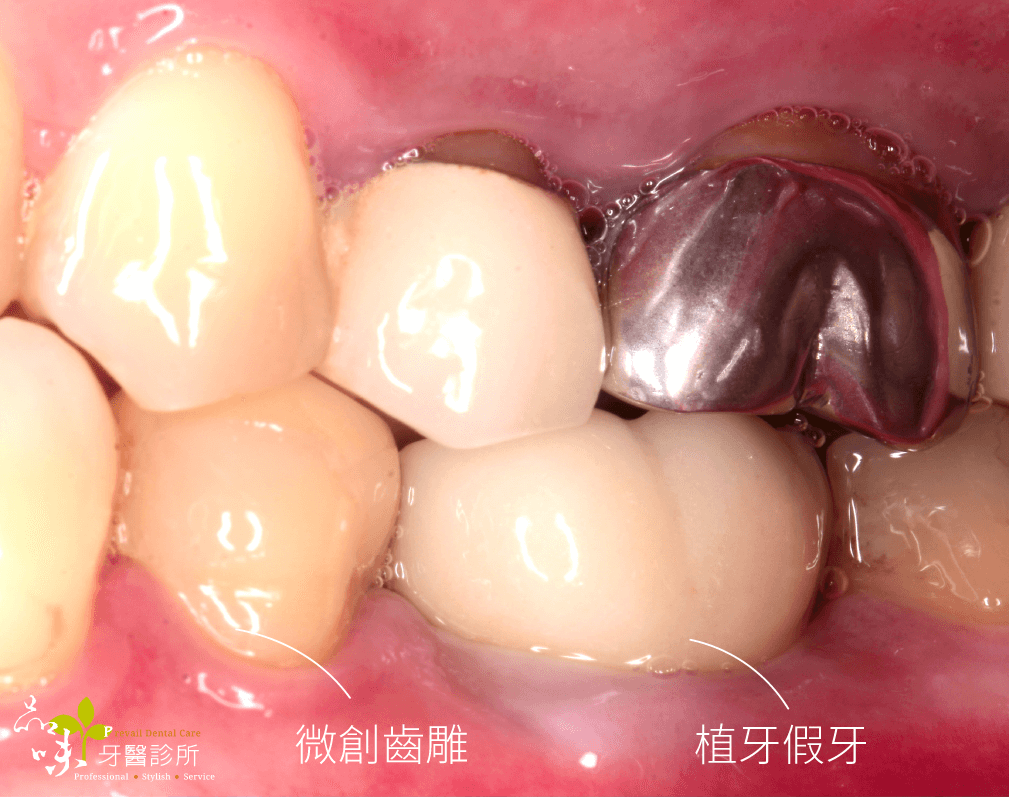

傷口在幾天後再也沒有疼痛感,後續回診追蹤也沒有不舒服。就這樣,四個月很快地過去了,假牙醫師幫他裝好全陶瓷的假牙。現在他可以開開心心地盡情享用美食。